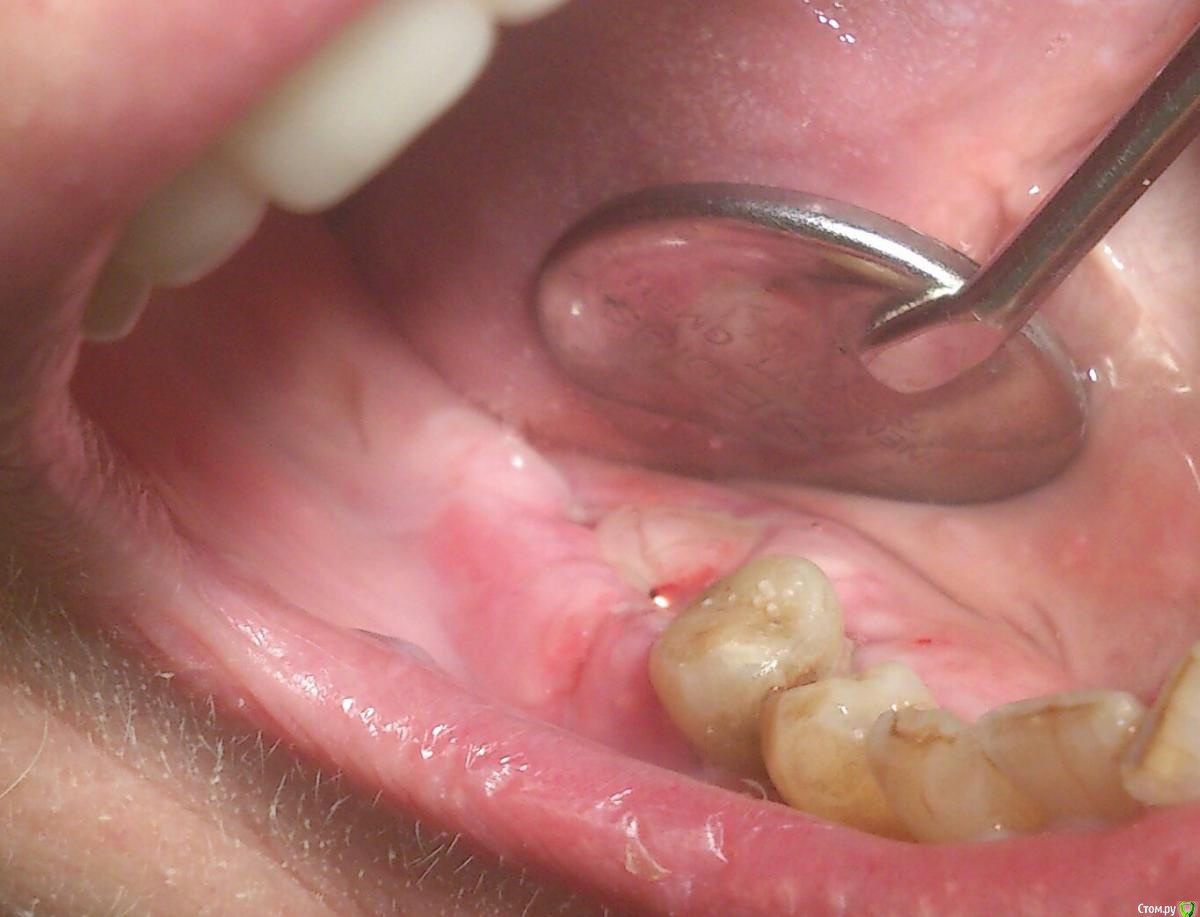

andrey_1965 Опубликовано 21 декабря, 2015 Поделиться Опубликовано 21 декабря, 2015 Ну как результат ?1.-диэпителизация подворот лоскута очень удобно,но опасно для резбы через неделю.язычно-механическая травма через 10 дней через 3недели. На временных доформирую рельеф.2. вроде ничего нештатного через 2недели A-PRF через 5недель убрал все,закрыл мембраной A-PRF две поперек,одна в доль через неделю через 13дней через 21день. Следующий осмотр будет на сроке 5 недель(думаю все сравняется) 3. через неделю 2недели 3недели,на дистальных отмываю помойку4 недели Ссылка на комментарий